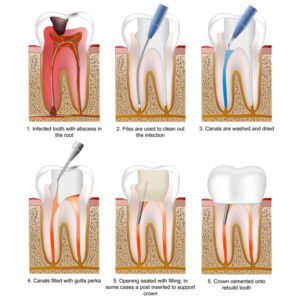

Root canal treatment is a proven dental procedure used to treat infection inside a tooth while preserving its natural structure. When deep decay, cracks, or trauma allow bacteria to reach the tooth pulp it can cause severe pain, swelling, and abscess formation. If left untreated, the infection may spread and result in tooth loss or serious oral health complications. At Suraksha Dental Clinic, we provide advanced root canal treatments that remove infection, relieve pain, and restore the tooth’s function—helping patients maintain a healthy, confident smile.

Visual guide explaining each stage of root canal treatment from infection removal to crown placement. 6. Clear Communication & Cost Transparency